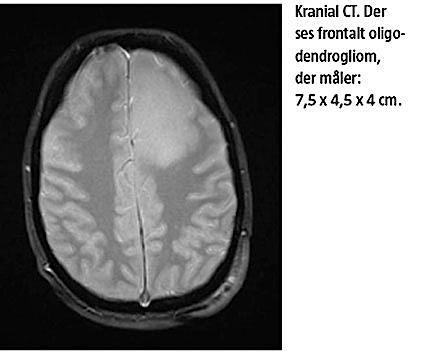

tioner: C-reaktivt protein 64 mg/l, leukocytter 12,1 mia./l, aspartataminotransferase 737 E/l og kreatininkinase 37.000 U/l. Der rekvireredes akut neurologisk tilsyn, hvor der efter oftalmoskopi blev fortaget lumbalpunktur, som afkræftede infektiøs ætiologi, men ved en efterfølgende akut kranial CT påvistes en venstresidig frontal tumor med perifokal ødemdannelse. Patienten blev herefter overflyttet til en neurologisk afdeling, og der blev påbegyndt højdosisprednisolonbehandling, hvorefter bevidsthedsniveauet normaliseredes i løbet af få dage. Der blev foretaget makroradikal resektion af et frontalt oligodendrogliom (WHO-II), som målte 7,5 × 4,5 × 4 cm. Ved en efterfølgende neuropsykologisk testning blev der påvist diskrete kognitive sequelae, men hun fortsatte sit universitetsstudie og har ikke haft behandlingskrævende psykopatologi siden (Figur 1).